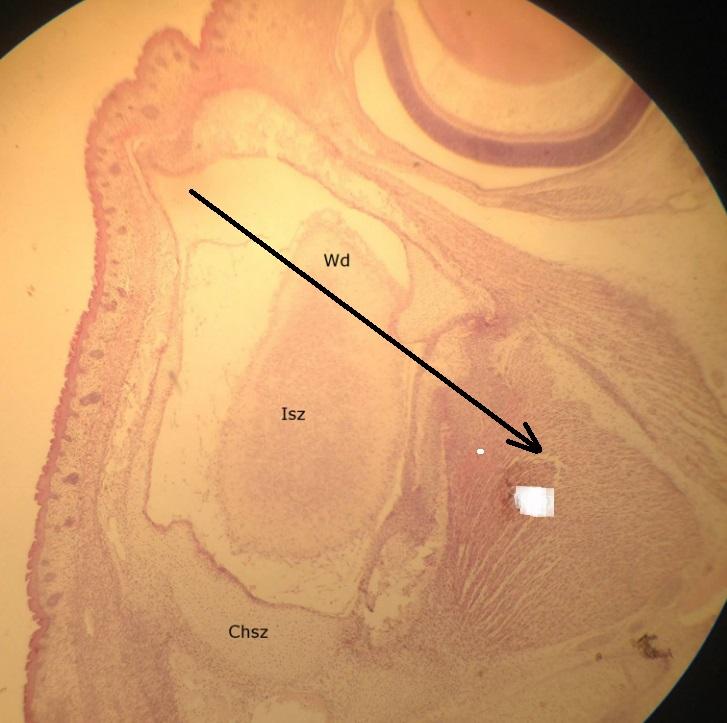

Pytanie 356

zawiązek zęba (preparat rozwojowy z głowy szczura, okolice zawiązka oka)